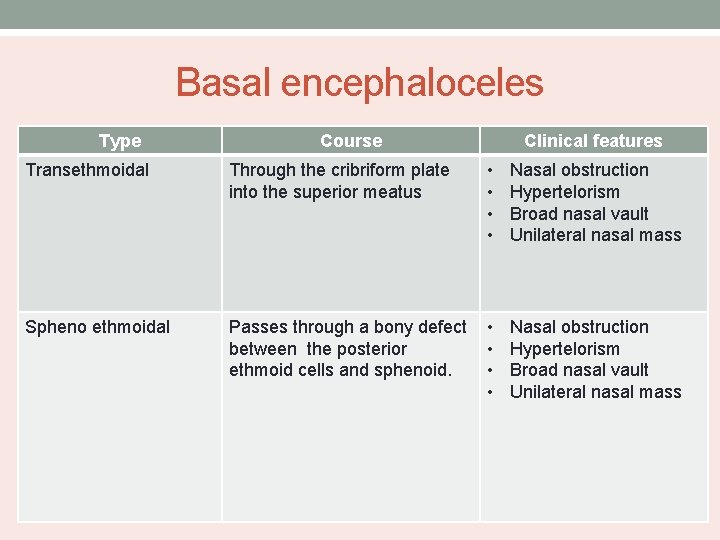

Basal encephaloceles Type Course Clinical features Transethmoidal Through the cribriform plate into the superior meatus • • Nasal obstruction Hypertelorism Broad nasal vault Unilateral nasal mass Spheno ethmoidal Passes through a bony defect between the posterior ethmoid cells and sphenoid. • • Nasal obstruction Hypertelorism Broad nasal vault Unilateral nasal mass